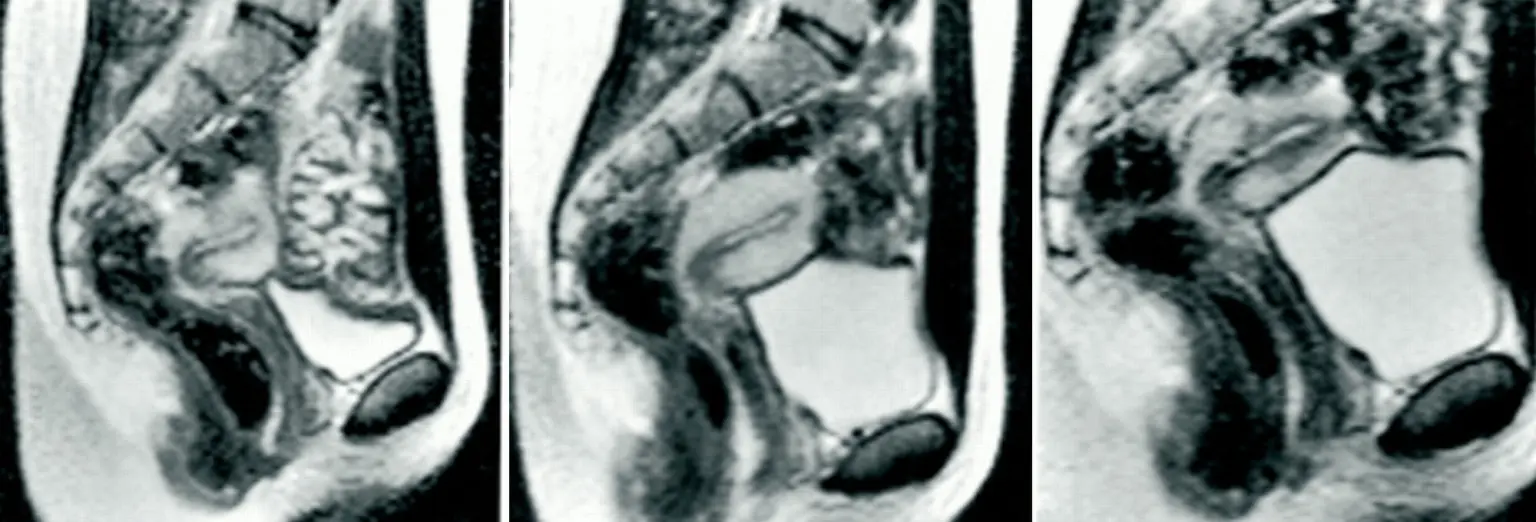

The initial experiment produced valuable information, but researchers wanted to gather more data. Over the following years, the study expanded to include additional volunteers.

Between 1991 and 1999, eight couples and three individual women participated in similar MRI experiments. In total, the machine captured images of intercourse thirteen more times.

Unlike the original couple, most participants attempted intercourse in the missionary position during the scans. Because the environment inside the MRI machine was not particularly comfortable or romantic, male participants were required to take medication to help maintain arousal during the study.

While analyzing the scans from these experiments, researchers noticed something unusual. In every recorded case, the woman’s bladder appeared to fill rapidly during intercourse.

This happened even when participants had used the bathroom shortly before entering the MRI machine. By the end of the scans, the images consistently showed a noticeably full bladder.

Scientists were intrigued by this observation because they did not fully understand why it occurred. The pattern appeared repeatedly across multiple participants and different scans.